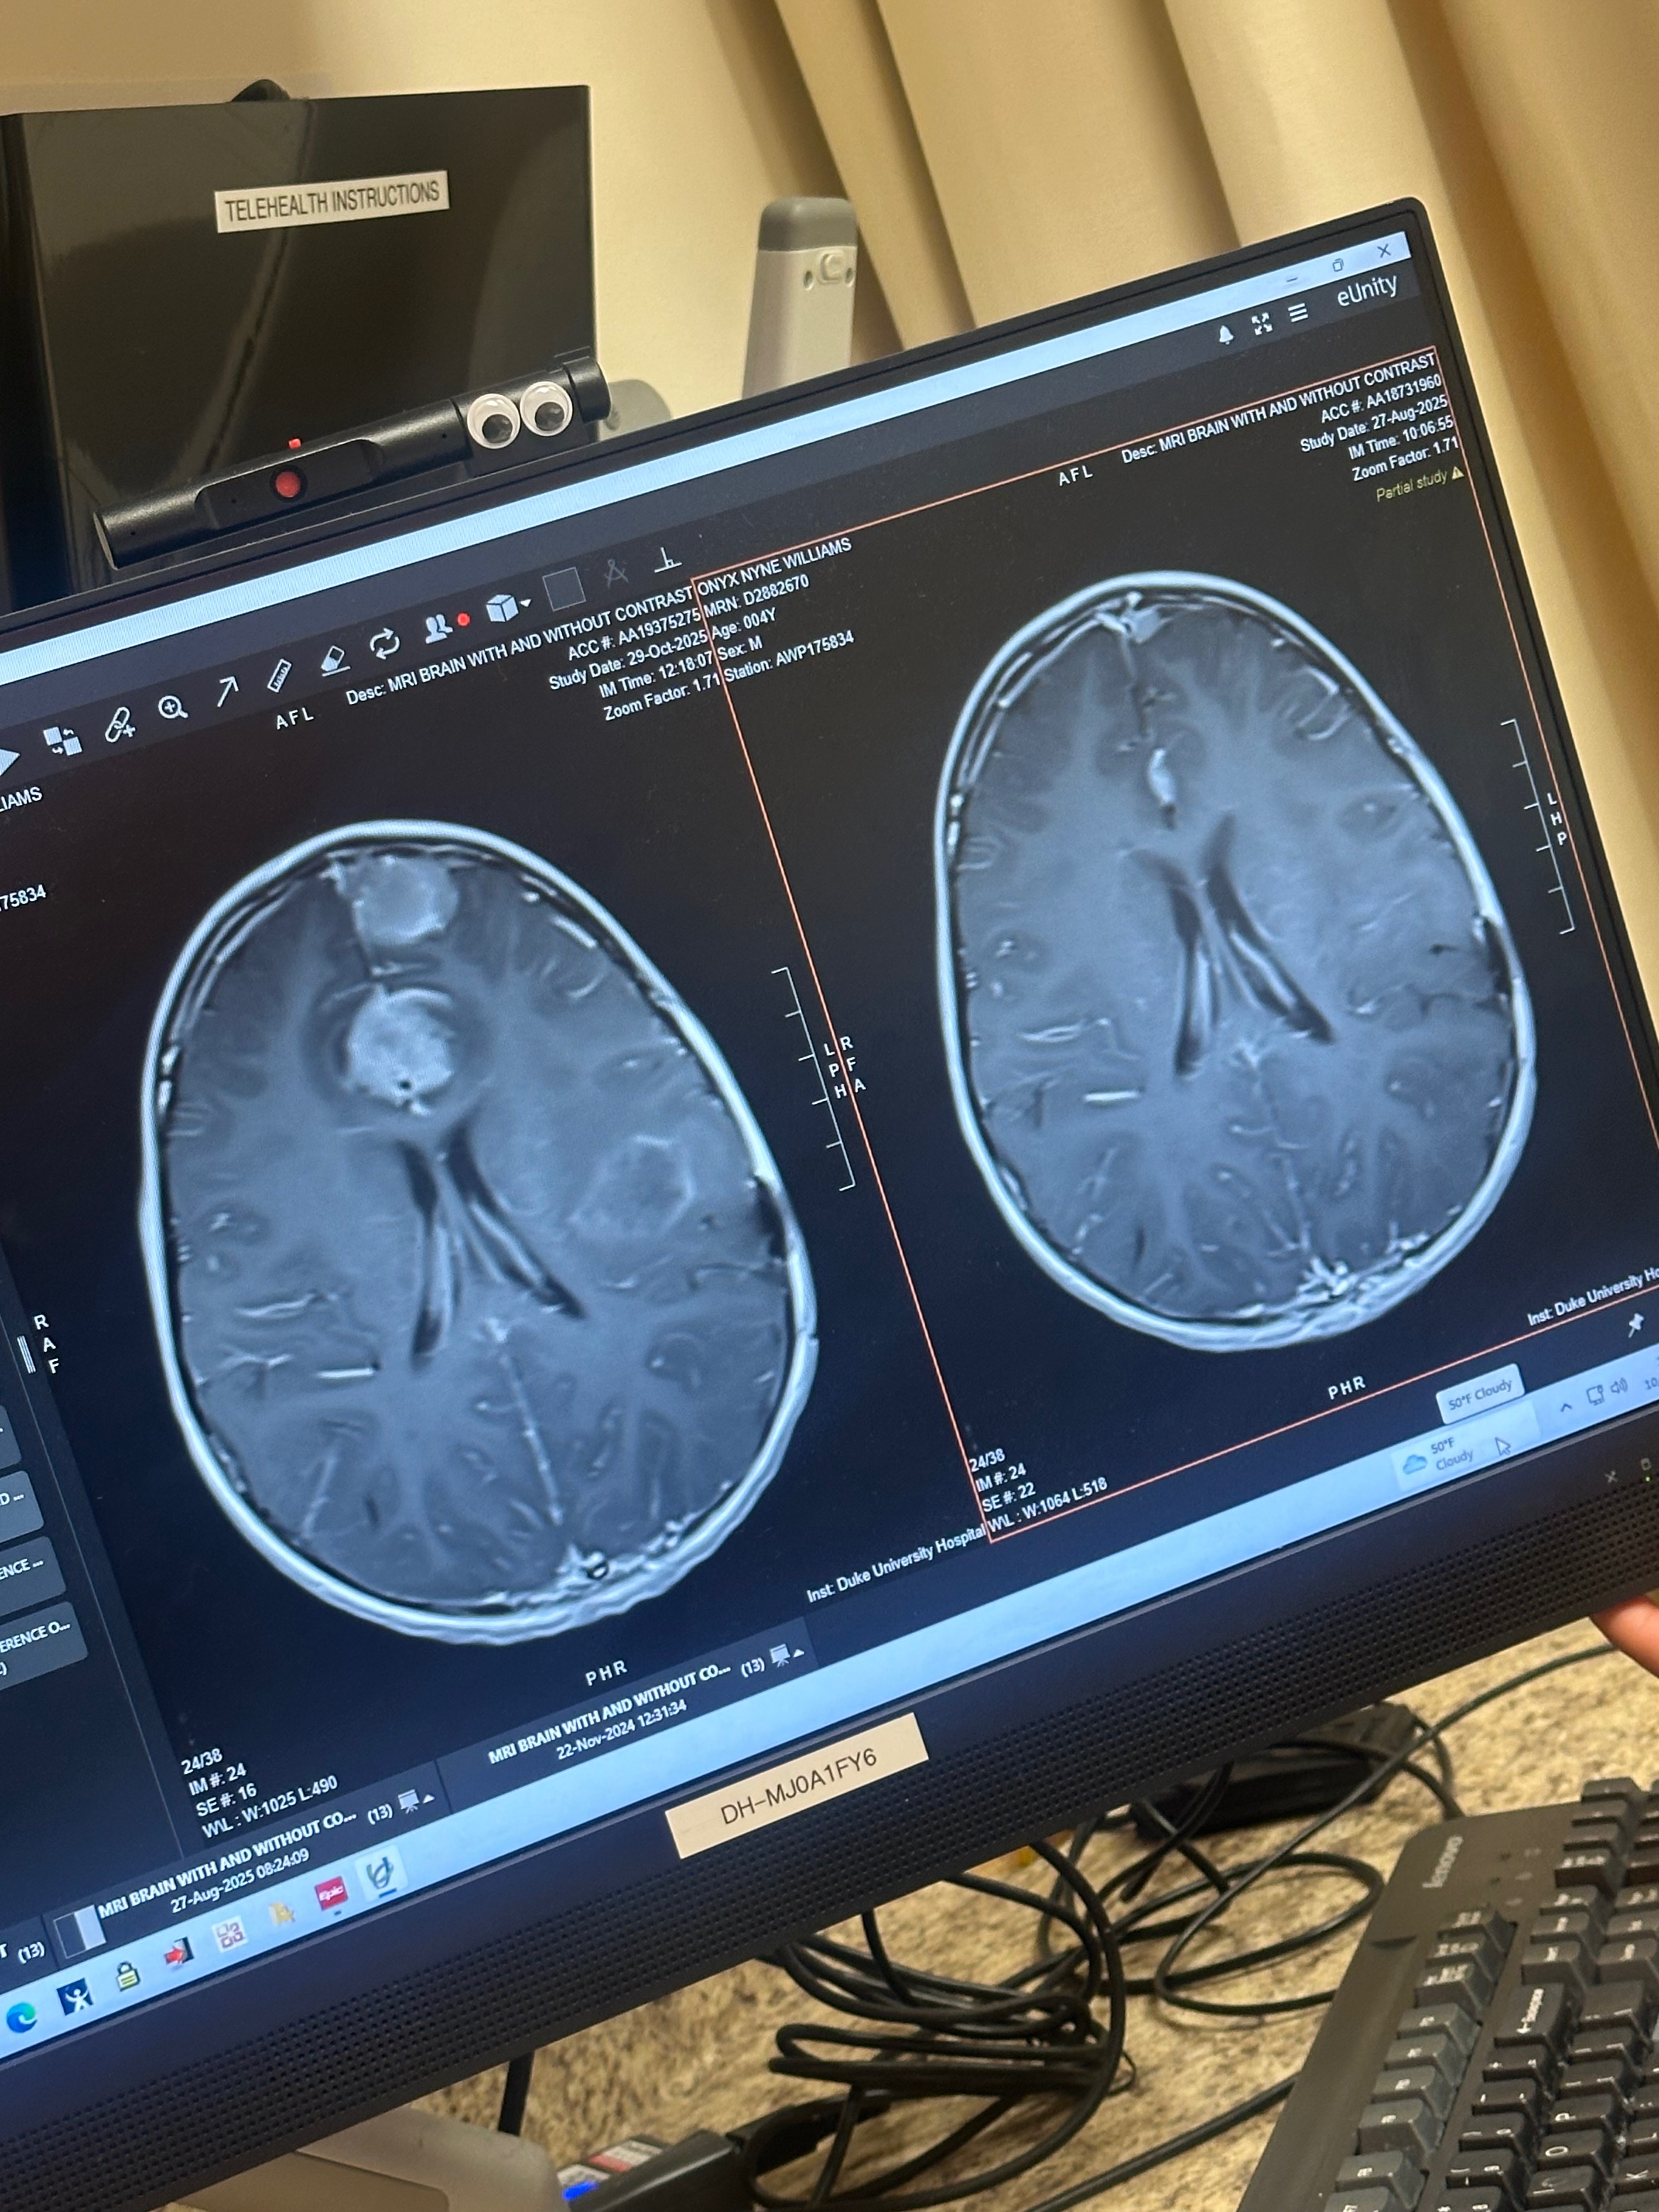

Hello again. Onyx is 4 years old and has been fighting his brain cancer hard this past year with radiation and treatments. We got recent news that the brain cancer has come back and is more aggressive than ever and now on his frontal lobes with two new tumors that are quite aggressive in growth. He was also diagnosed with leptomeningeal disease. Though he will be undergoing intensive radiation, the prognosis gives us limited time with Onyx. We know that God has the last word and we’re always praying that he beats this and pulls through! We are raising funds to make these moments special for him. He loves museums, video games, cars and marine animals! Our goal is to implement as much fun and enjoyment in his life. We don’t want him worried about all the hospital trips and treatments. As a family we also need funding because his mother is not able to work with how frequently we have to go to the doctor. We are asking for donations to make sure his dreams can come true and we can stay afloat as a family.